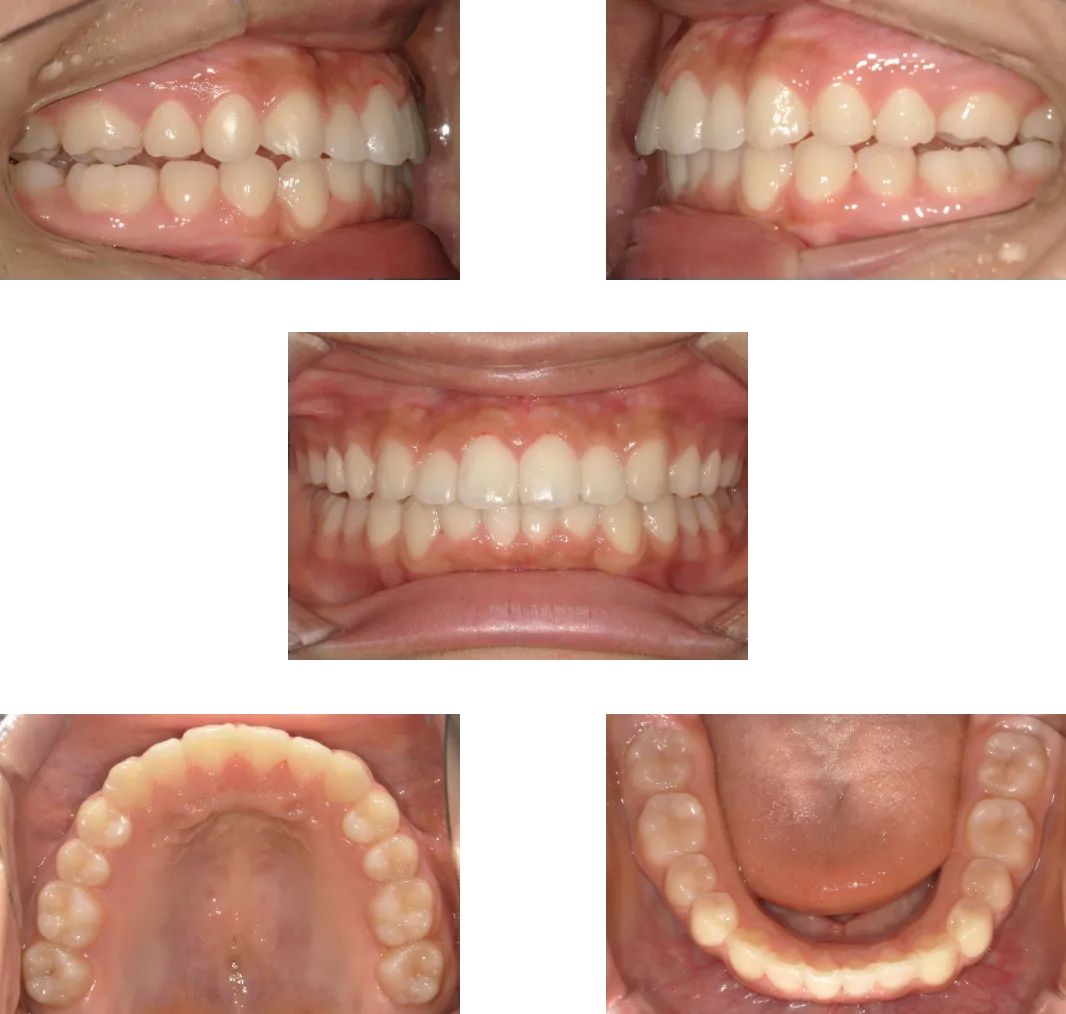

叢生 -39歳-

• Before

• After

診断

両側顎関節の変形

治療期間

1年6ヶ月+保定期間2年

料金

1,060,000円

抜歯

なし

リスク

痛み、軽度の歯根吸収、術後の変化